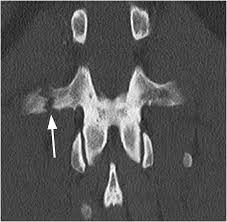

A transverse process fracture at the level of l5 is a surrogate marker of vertical instability of the pelvic fracture due to the attachment of the iliolumbar ligaments. Possible causes, signs and symptoms, standard treatment options and means of care and support. Transverse processes are used as lever arms by the deep spinal muscles to maintain posture and to induce rotation and lateral bending. It may occur as an avulsion fracture due to strong contracture of the muscles. Although the fracture is not associated with spinal cord damage and neurological deficits, the extreme force of the injury can cause visceral injuries and internal hemorrhage. The presence of other injuries might also be assessed due to the level of force needed to break the transverse process. In 78% of transverse process fractures, ct scanning showed that the fracture extended into the transverse foramen. Transverse process fractures caused by stress are likely under detected since even an acute transverse process fracture requires a high index of suspicion to be correctly identified(4,7). Here is an example of a patient with a benign looking transverse process fracture with an associated significant injury to the back. Transverse process fracture you have fractured a transverse process. Thoracic transverse process fractures (ttpfs) are injuries that go unnoticed during traditional autopsies, as demonstrated by a lack of medicolegal publications regarding ttpfs. We retrospectively reviewed the reports of lumbar spine and abdominopelvic ct scans from 2017 and 2018 to classify the types of spine fractures, their mechanism of injury, treatment and. Up to 60% of lumbar transverse process fractures identified on ct will be missed on plain radiographs.

Defined as those involving the transverse process only, without extension into the pedicle, lamina, or facet complex.

Defined as those involving the transverse process only, without extension into the pedicle, lamina, or facet complex. There are two transverse processes that extend off each vertebra in the spine, one on each side. Thoracic transverse process fractures (ttpfs) are injuries that go unnoticed during traditional autopsies, as demonstrated by a lack of ct scans showed transverse process fractures in 39 (7.3%) patients. This part extends out from the side of the main body of the bone (called the vertebral body). Thoracic transverse process fractures (ttpfs) are injuries that go unnoticed during traditional autopsies, as demonstrated by a lack of medicolegal publications regarding ttpfs.